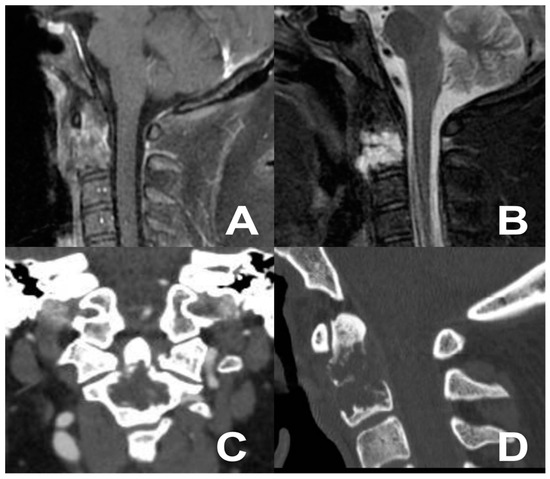

3.4. Third Case: Two-Staged Transoral Approach and Posterior Midline Occipitocervical Fusion—Subtemporal/Infratemporal and Retrosigmoid Approaches for Tumor Relapse